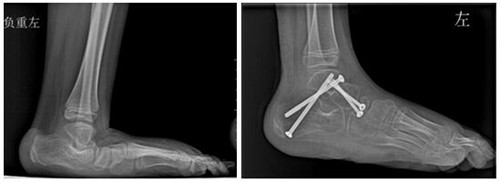

尹靖宇主任详细告知颜颜爸爸妈妈病情、手术的方式和难度、术后可能出现的并发症,颜颜的爸妈同意先行纠正左侧足踝畸形。完善相关检查后,在全麻下行“左侧跟腱延长+跟距关节、舟距关节融合+管型石膏外固定术”,手术顺利,并用克氏针分别穿刺跟骨和距骨关节面、距骨和舟骨关节面,透视下见对位良好,取松质骨空心螺钉分别固定,逐层缝合切口。

术后,给予小腿管型石膏外固定正中位,叮嘱禁止左侧下肢负重站立、行走,并坚持双侧下肢直腿抬高练习。如期拆除石膏外固定并给予拆除伤口缝线,尹靖宇主任再次为颜颜查体,其左侧踝关节活动度良好。

▲术前DR ▲术后DR